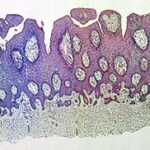

Atlas of skin histopathology

Inflammatory papillary hyperplasia =فرط التصنع الحليمي الالتهابي